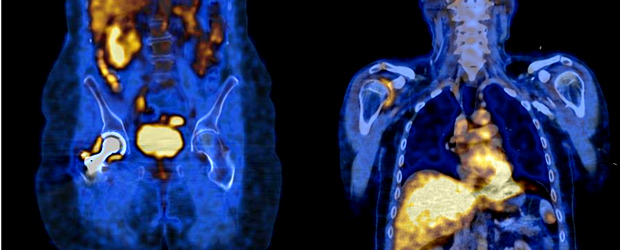

Es común la visualización de fibromas uterinos, así como captación ovárica y tenue captación en mamas. En la figura 2 se presenta un caso de actividad ovárica normal con un SUV máximo de 4.0.